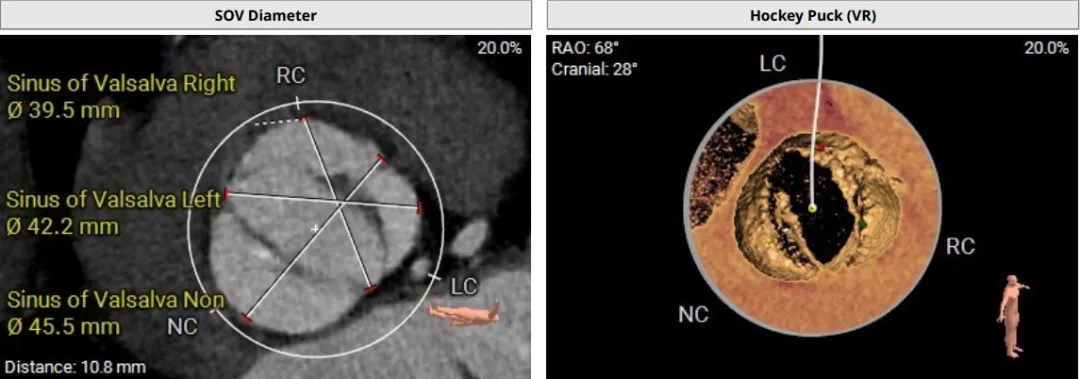

该患者术前CT评估提示:主动脉瓣Type-I型,瓣叶稍增厚,左右冠窦瓣叶交界粘连,无冠窦瓣叶轻微钙化,存在三个瓣窦,分布不均匀,左右冠窦融合;主动脉瓣环周长折算直径32.6mm;左心室流出道周长折算直径32.0mm,无钙化,无狭窄;STJ直径36.2mm,升主动脉直径38.6mm;左侧冠脉10.4mm ,瓣叶长10.8mm;右侧冠脉18.7mm,瓣叶长11.2mm;双侧冠脉开口高度可,无钙化;心尖-主动脉夹角偏大,左室主动脉夹角为120°;